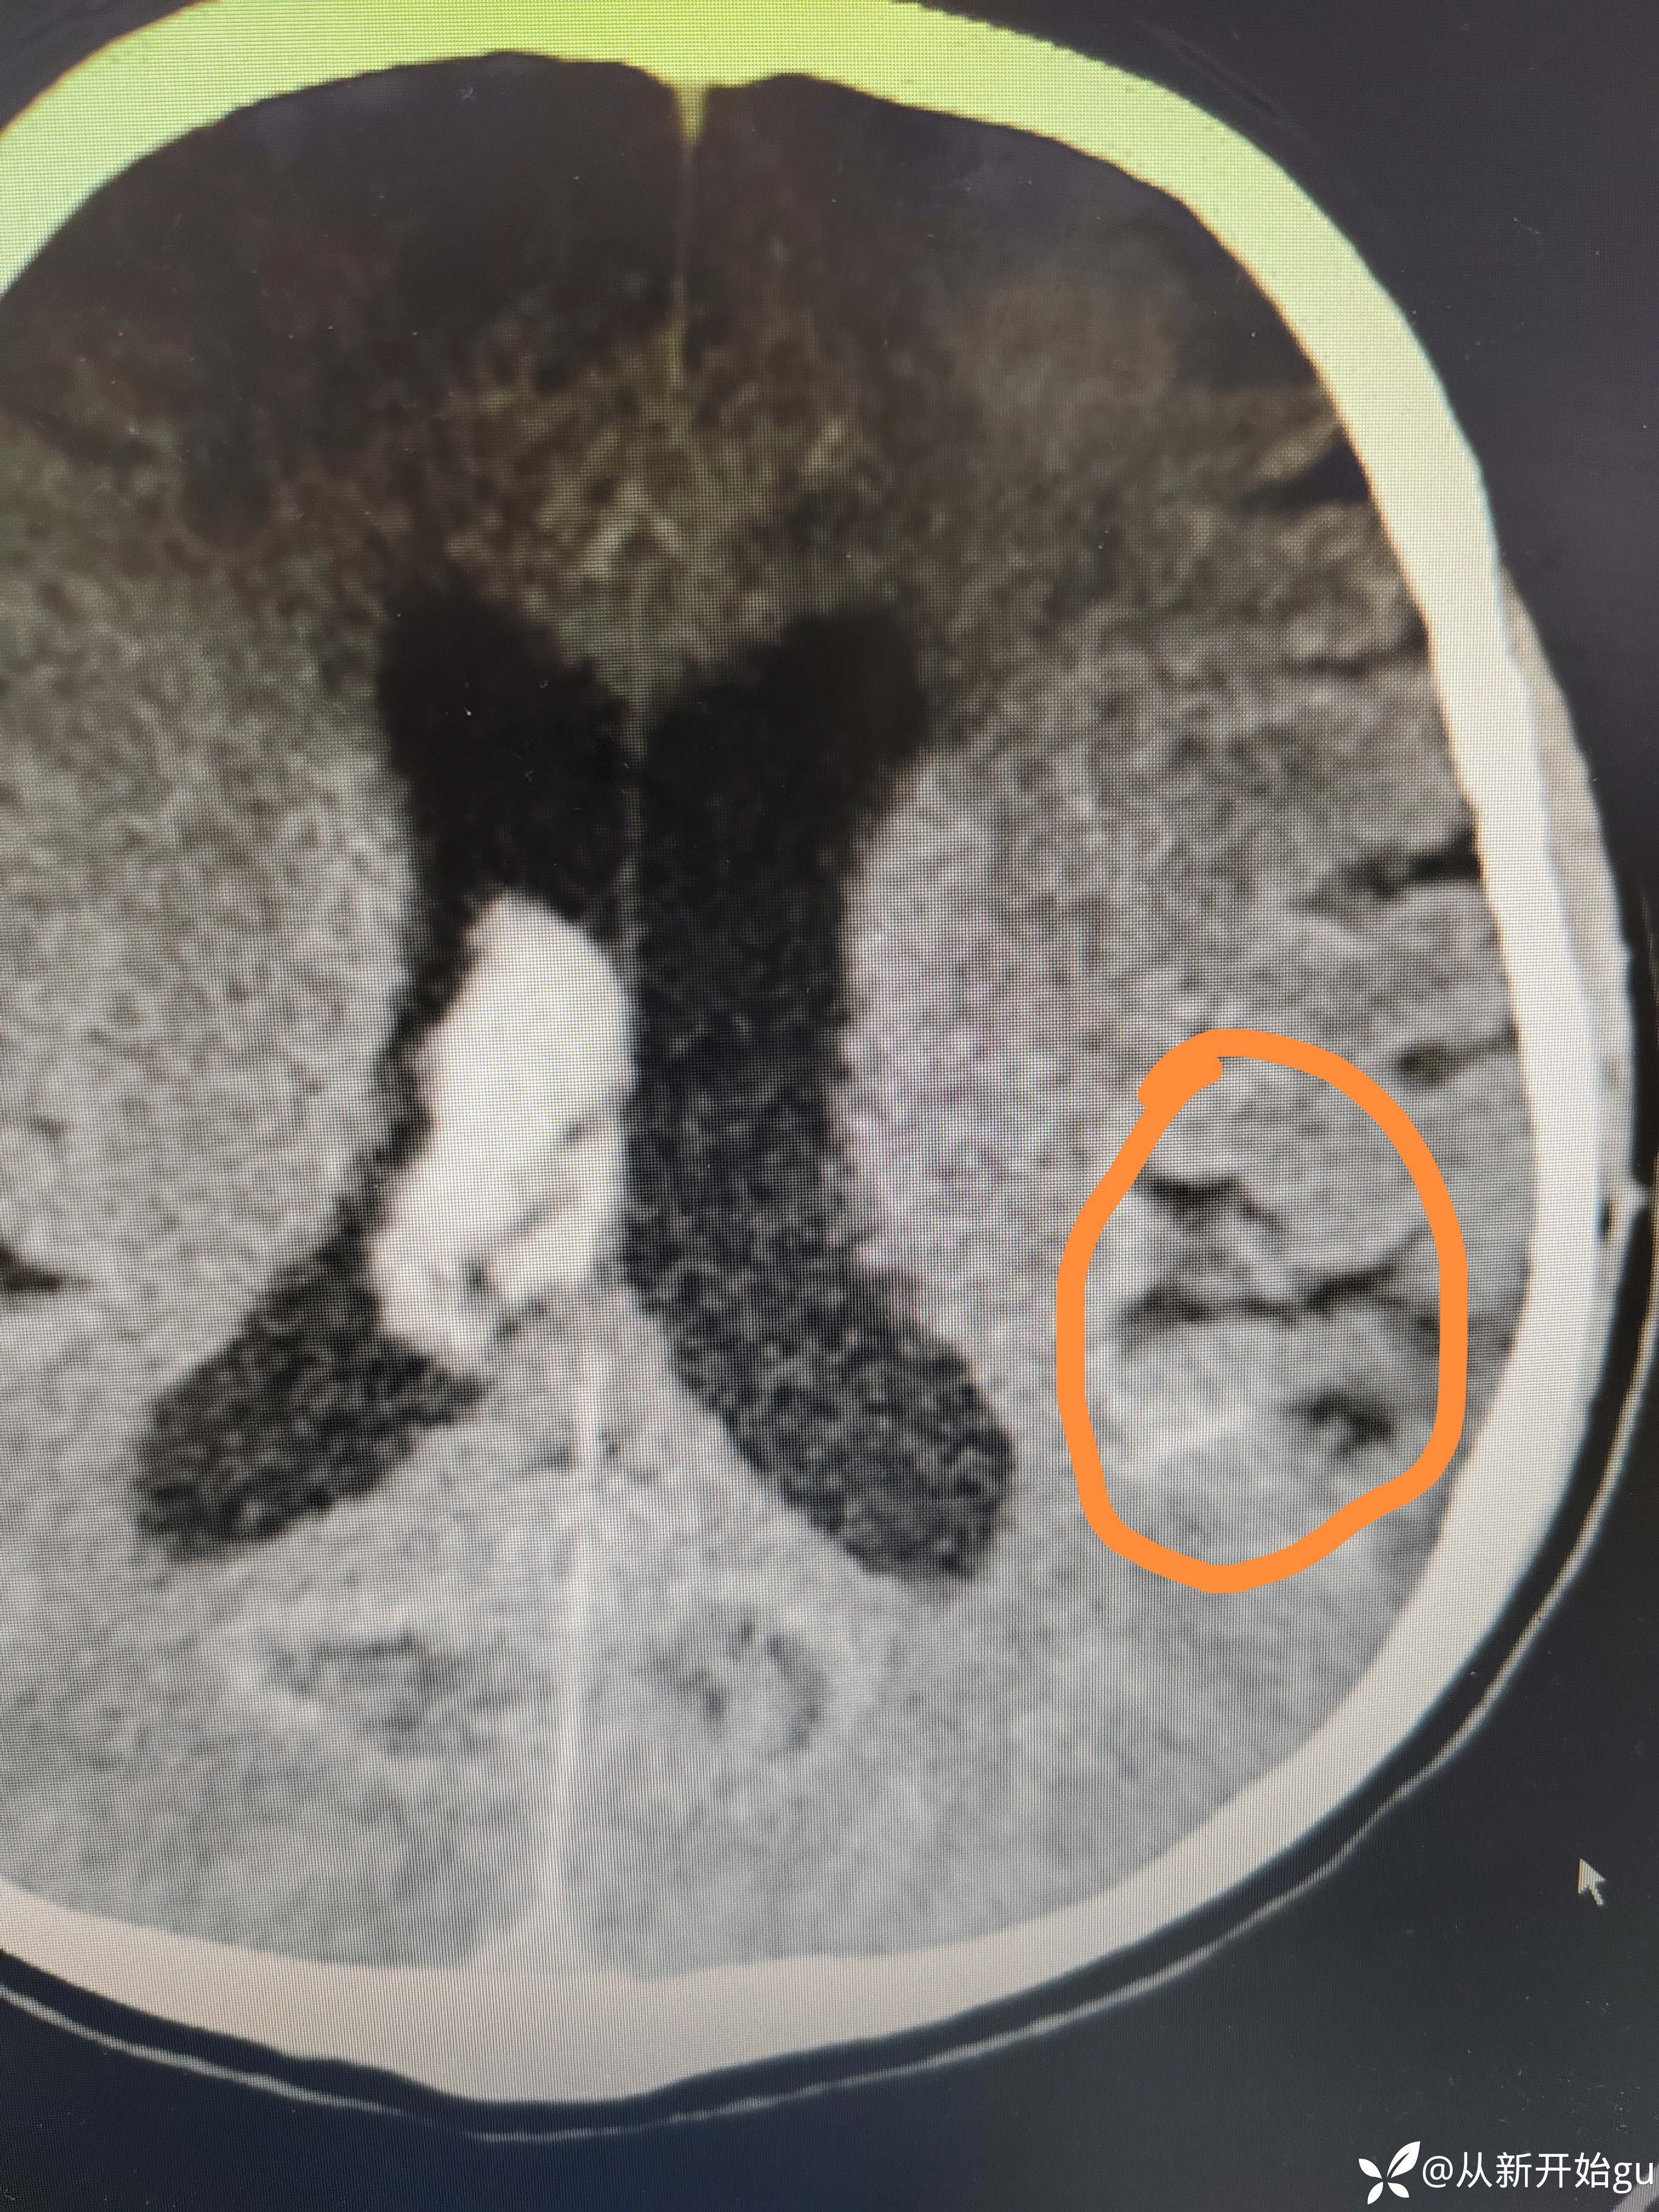

6天后颅脑CT.

6天后颅脑CT.